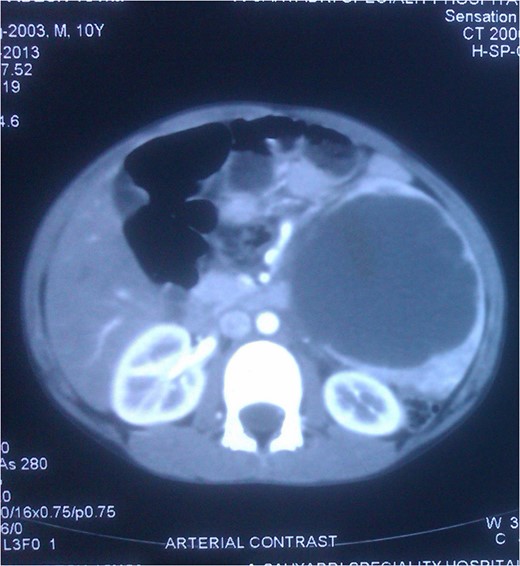

Hemoglobin, leucocyte and platelet counts were normal. Ultrasonography revealed a large hypoechoic cystic lesion involving the spleen measuring 108 × 98 mm with thin internal septa. CT scan—A large well-defined cystic lesion with few thin enhancing septa within it is seen involving the spleen. The lesion is causing mass effect and displacing adjacent vessels and bowel loops (Figs 1, 2).

CT Scan: Cross section showing the splenic mass almost reaching the midline.